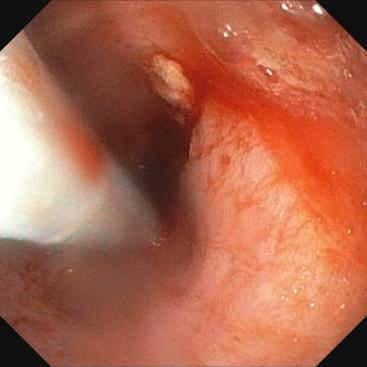

近日,pilipili 消化内科接诊了一位因胰胃间隙恶性肿瘤、食管狭窄,无法进食的91岁营养不良患者。患者入院后,在进行更换胃管时,发现普通胃管已无法通过,行胃镜检查中发现狭窄明显。经过院内专家团队的评估,决定采用超细胃镜尝试,并成功放置了空肠管。针对该患者高龄、身体虚弱、营养不良等实际情况,经与家属沟通,同意行内镜下放置食管支撑架。手术由陈东副主任医师和陈达主治医师完成,术后患者的食管狭窄得到缓解,可自主进食,生活质量得到了显著提升。